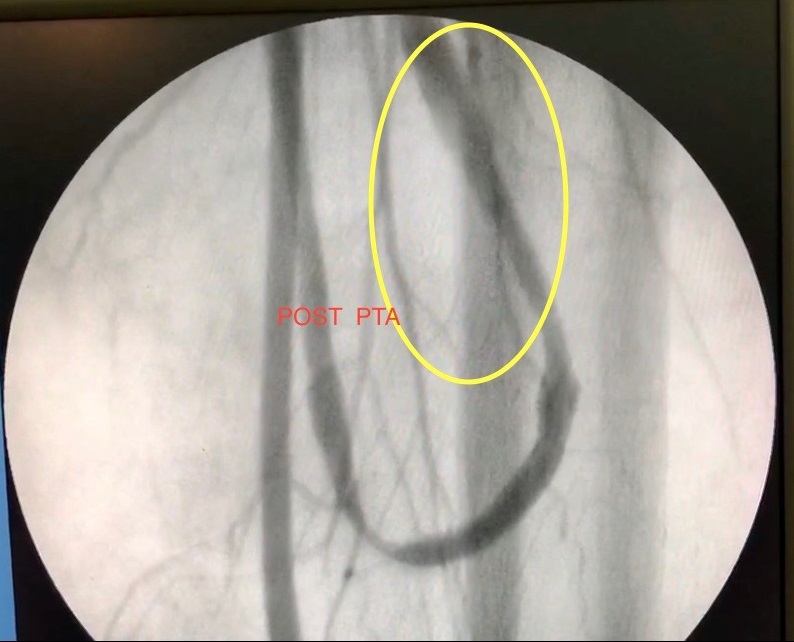

Se realizó una primera dilatación con balón simple de 5 x 60, durante 120 segundos continuos a 8 ATM. Control angiográfico: constató dilatación con pequeño flap de disección (Imagen 4). Se procedió a realizar angioplastía con balón con Paclitaxcel de 6 x 60 RANGER®, durante 180 segundos a 6 ATM, obteniendo resultado satisfactorio con buen flujo en el recorrido completo de todo el acceso sin necesidad de colocar stent.

Se obtuvo resultado satisfactorio con buen flujo en el recorrido completo de todo el acceso, mediante control angiográfico (Imagen 5 . 6).